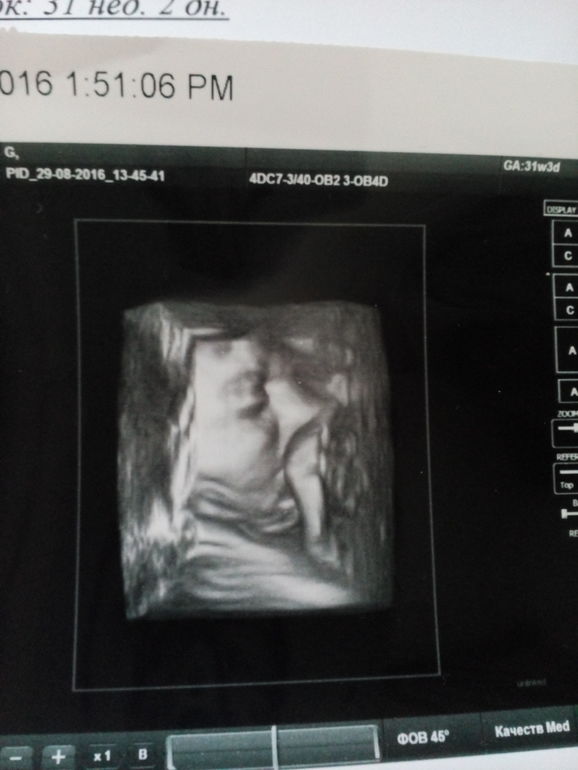

Наше третье УЗИ.

УЗИ, КТГ, доплерНу вот мы и съездили на третью встречу с пузожителем.И нам сказали,что у нас 100% будет девочка

По УЗИ врач сказал всё тфу тфу идеально,придраться не к чему,предлежание головное.

Но как и старшая дочка будет крошечкой.Вес 1625 гр.ЧСС-160 в мин.

По месячным сегодня 31 нед.2 дн,а по УЗИ 30 нед.4 дня.Легкие 1 ст.зрелости.

Наша красавица всё УЗИ сосала пальчик)И Закрывала личико ручками.А ещё очень сильно пинала дядю узиста ножками)И улыбалась.